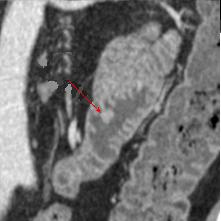

Lipome siegent portion ileo-

coecale . Image TDM en coupe sagitale ( fleche rouge

) |